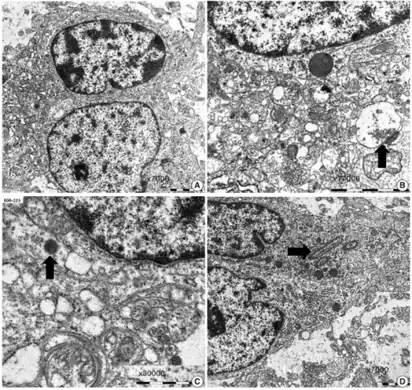

a-d)Ultrastructural findings of dysembryoplastic neuroepithelial tumors -